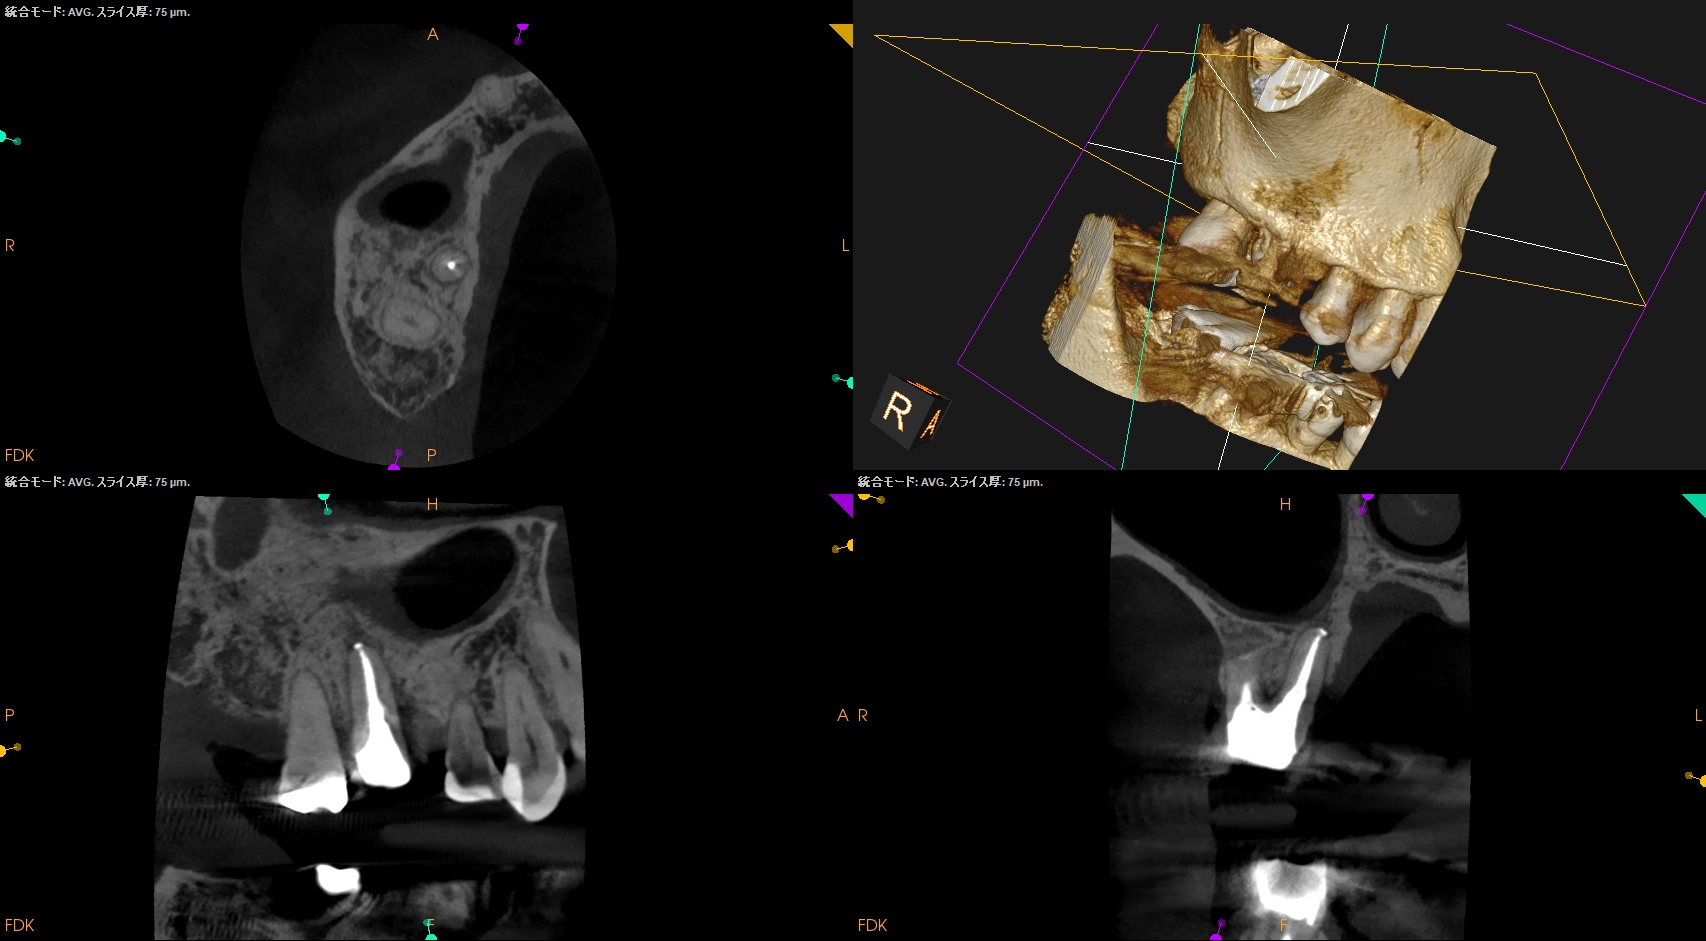

術後にPA, CBCTを撮影した。

MB

DB

B

問題はないだろう。

#3 MB, DB Apicoectomy 7M recall(2026.3.30)

P

7ヶ月前と比較した。

劇的に歯槽骨の開創は回復している。

そしてP根だが、根尖病変の治癒とともに口蓋側の骨欠損が大きく回復しているのがわかる。

これは単純にエンドだけの問題であったのだ。

エンドの治療のみでここまで回復していることがこの歯内療法の治療のパワーを示している。

HyFlex EDM #60.02でわずか数mm形成しただけなのに、ここまで歯槽骨が回復している。